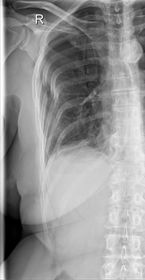

| AP Shoulder | patient is rotated towards the unaffected shoulder: decreased thoracic superimposition over the scapular body |

| AP Shoulder | patient is rotated towards affected side:increased thoracic superimposition over the scapular body |